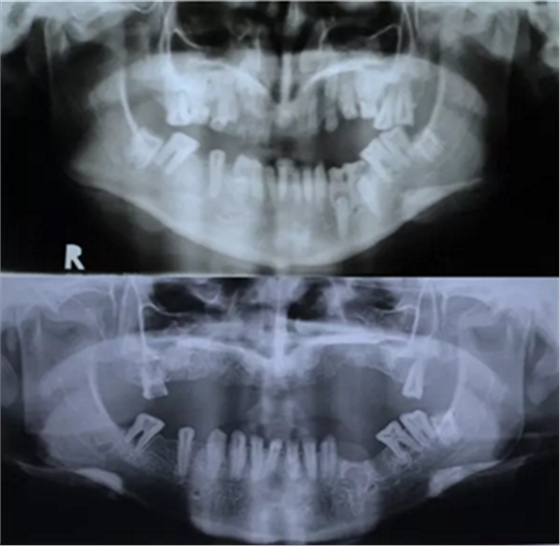

该患者 12 岁时已诊断为釉质发育不全。家族史正常,否认全身系统性疾病。全身系统检查无明显异常,检查双侧颞下颌关节、开口度正常。口内及 X 片检查见上颌缩窄,上颌牙列缺失,安氏三类错牙合,下颌牙牙冠短小,牙根正常。上颌大量牙槽骨因以前手术干预而丧失,后牙区牙槽骨高于前牙区。病变牙齿在之前的治疗中已被拔除。

图 2. 曲面断层片(术前、拔牙后、种牙后)